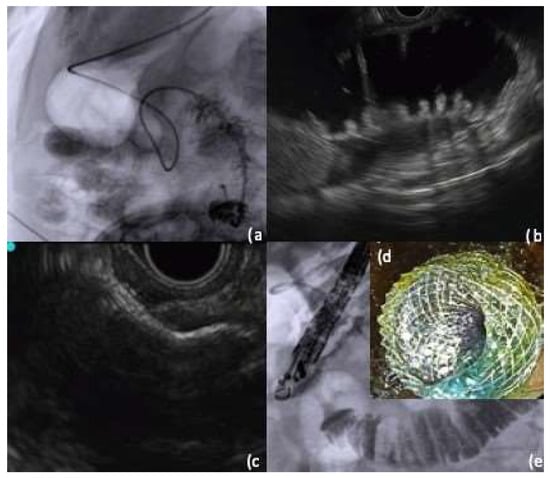

5.2.2. Endoscopic Ultrasound Double Balloon-Assisted Technique

- Itoi, T.; Itokawa, F.; Uraoka, T.; Gotoda, T.; Horii, J.; Goto, O.; Moriyasu, F.; Moon, J.H.; Kitagawa, Y.; Yahagi, N. Novel EUS-guided gastrojejunostomy technique using a new double-balloon enteric tube and lumen-apposing metal stent (with videos). Gastrointest. Endosc. 2013, 78, 934–939. [Google Scholar] [CrossRef] [PubMed]